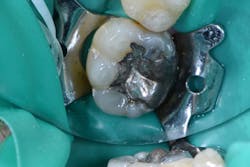

Figure 3: Existing No. 30 OL amalgam with recurrent decay

A 50-year-old male patient presented for restoration on tooth No. 30 that was found on a recent exam to have recurrent decay (figure 3). The patient’s medical history was unremarkable. He was having no pain or sensitivity. Although the existing restoration was large, and the possibility of indirect restorations was discussed, the patient was only interested in a direct resin restoration.